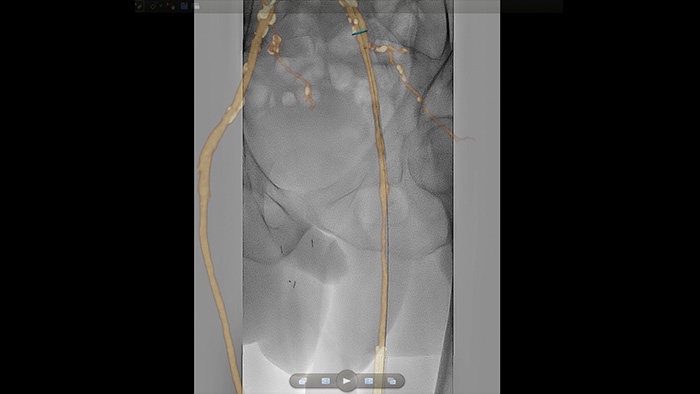

SmartCT Roadmap overlays a 3D reconstruction using SmartCT Angio or SmartCT Soft Tissue, to emphasise target vessel and lesions, aiding guidewire and catheter navigation through complex vessel structures. All controlled via the touch screen at the table.

VesselNavigator provides an intuitive and continuous 3D roadmap based on existing CTA and MRA datasets to guide you through vasculature during peripheral procedures.